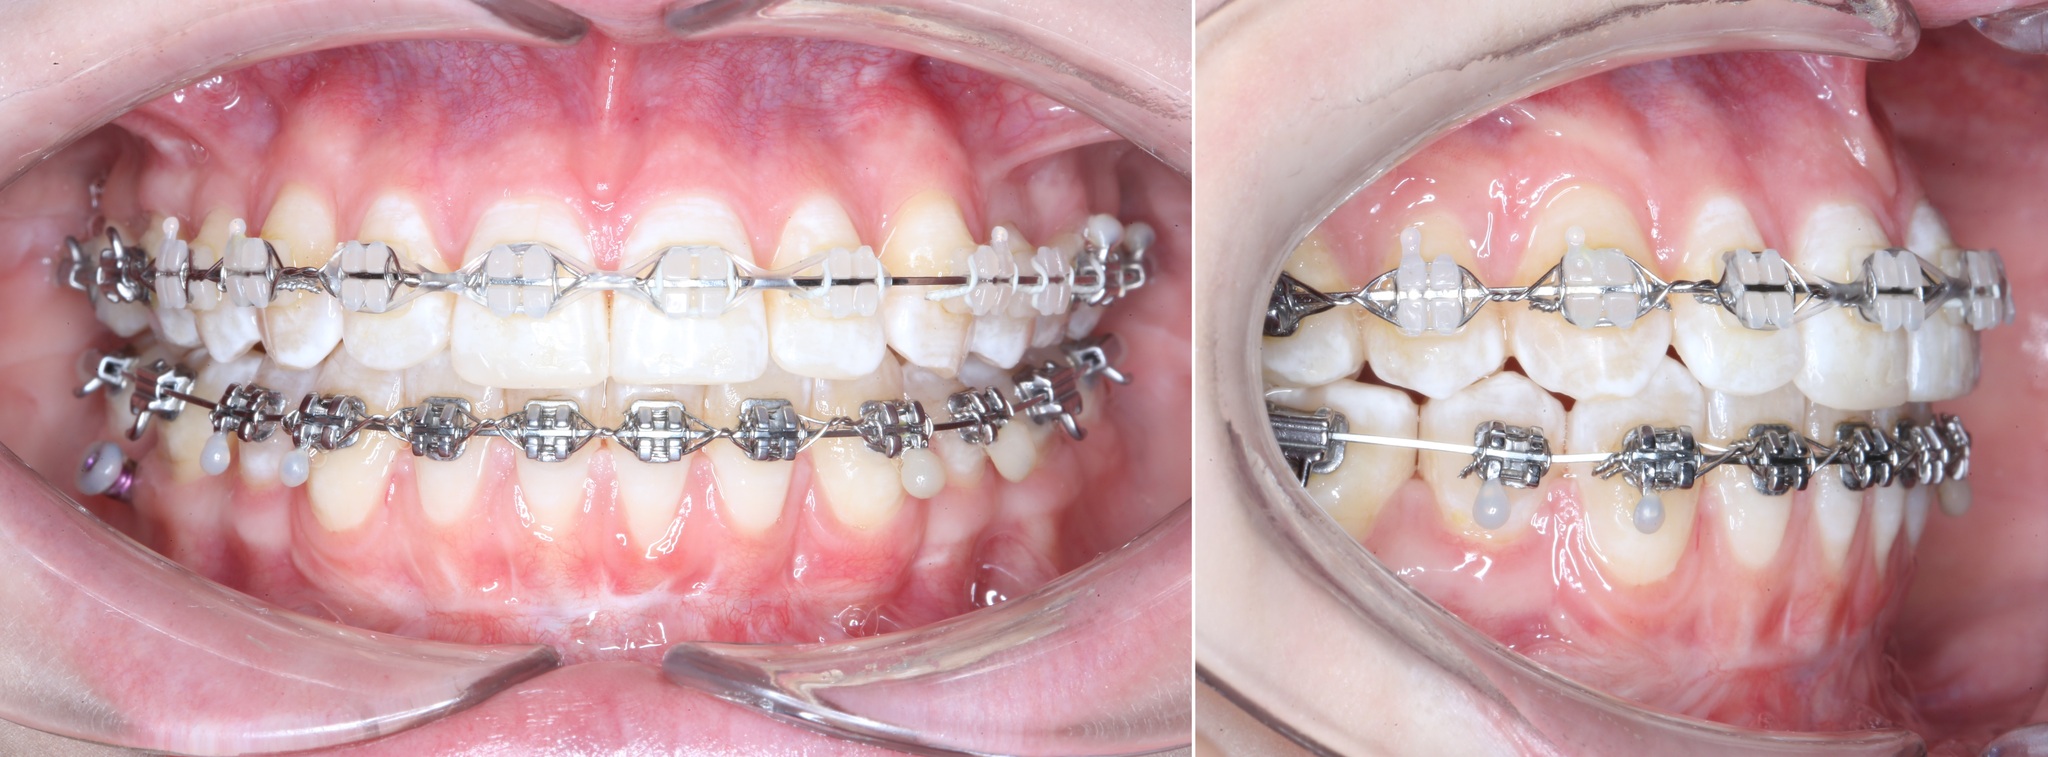

После снятия швов через несколько месяцев область операции выглядит так:

Рубец будет потихоньку разглаживаться.

Сравним:

Вот так и выглядит операция – вестибулопластика.